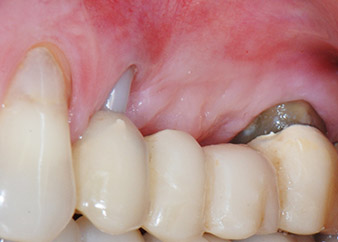

Two-months interim result

Figures 17 and 18 show the clinical result two months after the surgery. Tooth 24 exhibited reduced mobility of Miller class 1, and the soft tissues were free of inflammation. Probing was avoided at this point of time to prevent reinfection and to avoid violating the epithelial attachment. A control visit was scheduled for reentry and placement of healing abutments, six months after the insertion of the implants.

Two months after the surgery, the patient was pain-free.

Fig. 17: Two months after the surgery, the patient was pain-free and the area was free of inflammation.

after the surgery

Fig. 18: Tooth 24 now showed less mobility.

At the two-months recall, the mobility of the remaining “dental element” 24 was already reduced from Miller 2 to Miller 1. The soft tissue attachment was on the level of the neighbouring tooth 23. Moreover, there were no endodontic or periodontal symptoms, so its prognosis may have to be readjusted.

However, as most of the buccal and proximal bone is missing and the composite build-up extends to the apical section of the root, a higher reattachment level is not to be expected due to biologic reasons (Sculean et al., 2008).